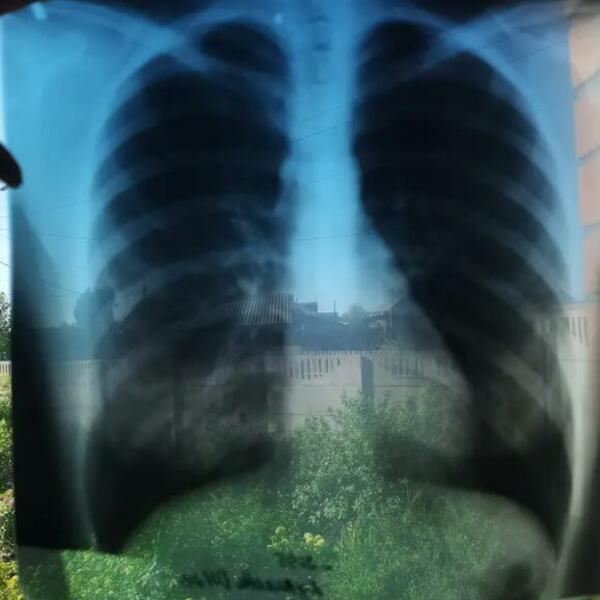

A otkriva se uz pomoć rengenskih snimaka, MRI ili ultrazvuka.

Ona je imala samo 14 godina kada su joj otkrili da joj se srce nalazi na desnoj strani tela. Zatim četiri godine kasnije, sa 18 godina rečeno joj je da joj se jetra nalazi takođe na desnoj strani tela. A zbog upale pluća koja ju je zadesila 2019. godine lekari su joj otkrili da su pluća locirali uz pomoć reflekta ogledala.